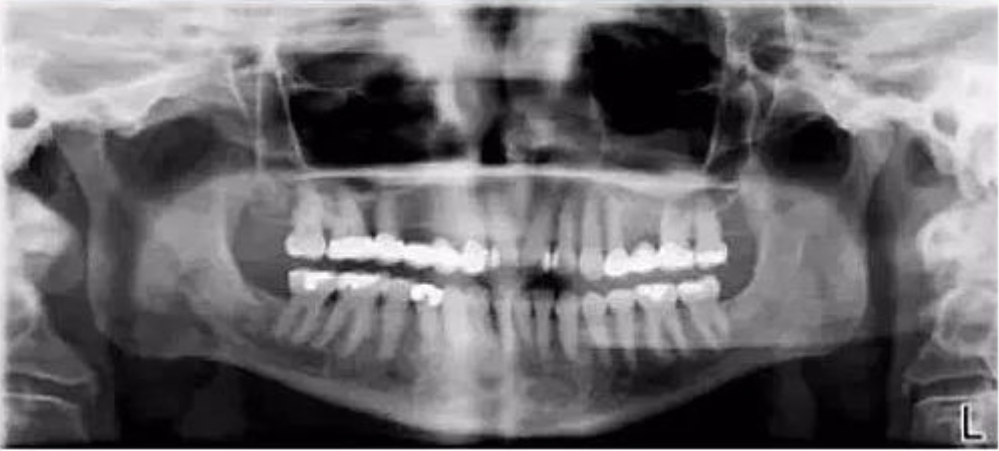

十、上颌区拱状阴影

【失误原因】

患者舌腭之间有空隙,在案例影像中可明显看到一个上颌拱形阴影。

【解决方法】

让患者闭口且保持舌头顶住上腭。